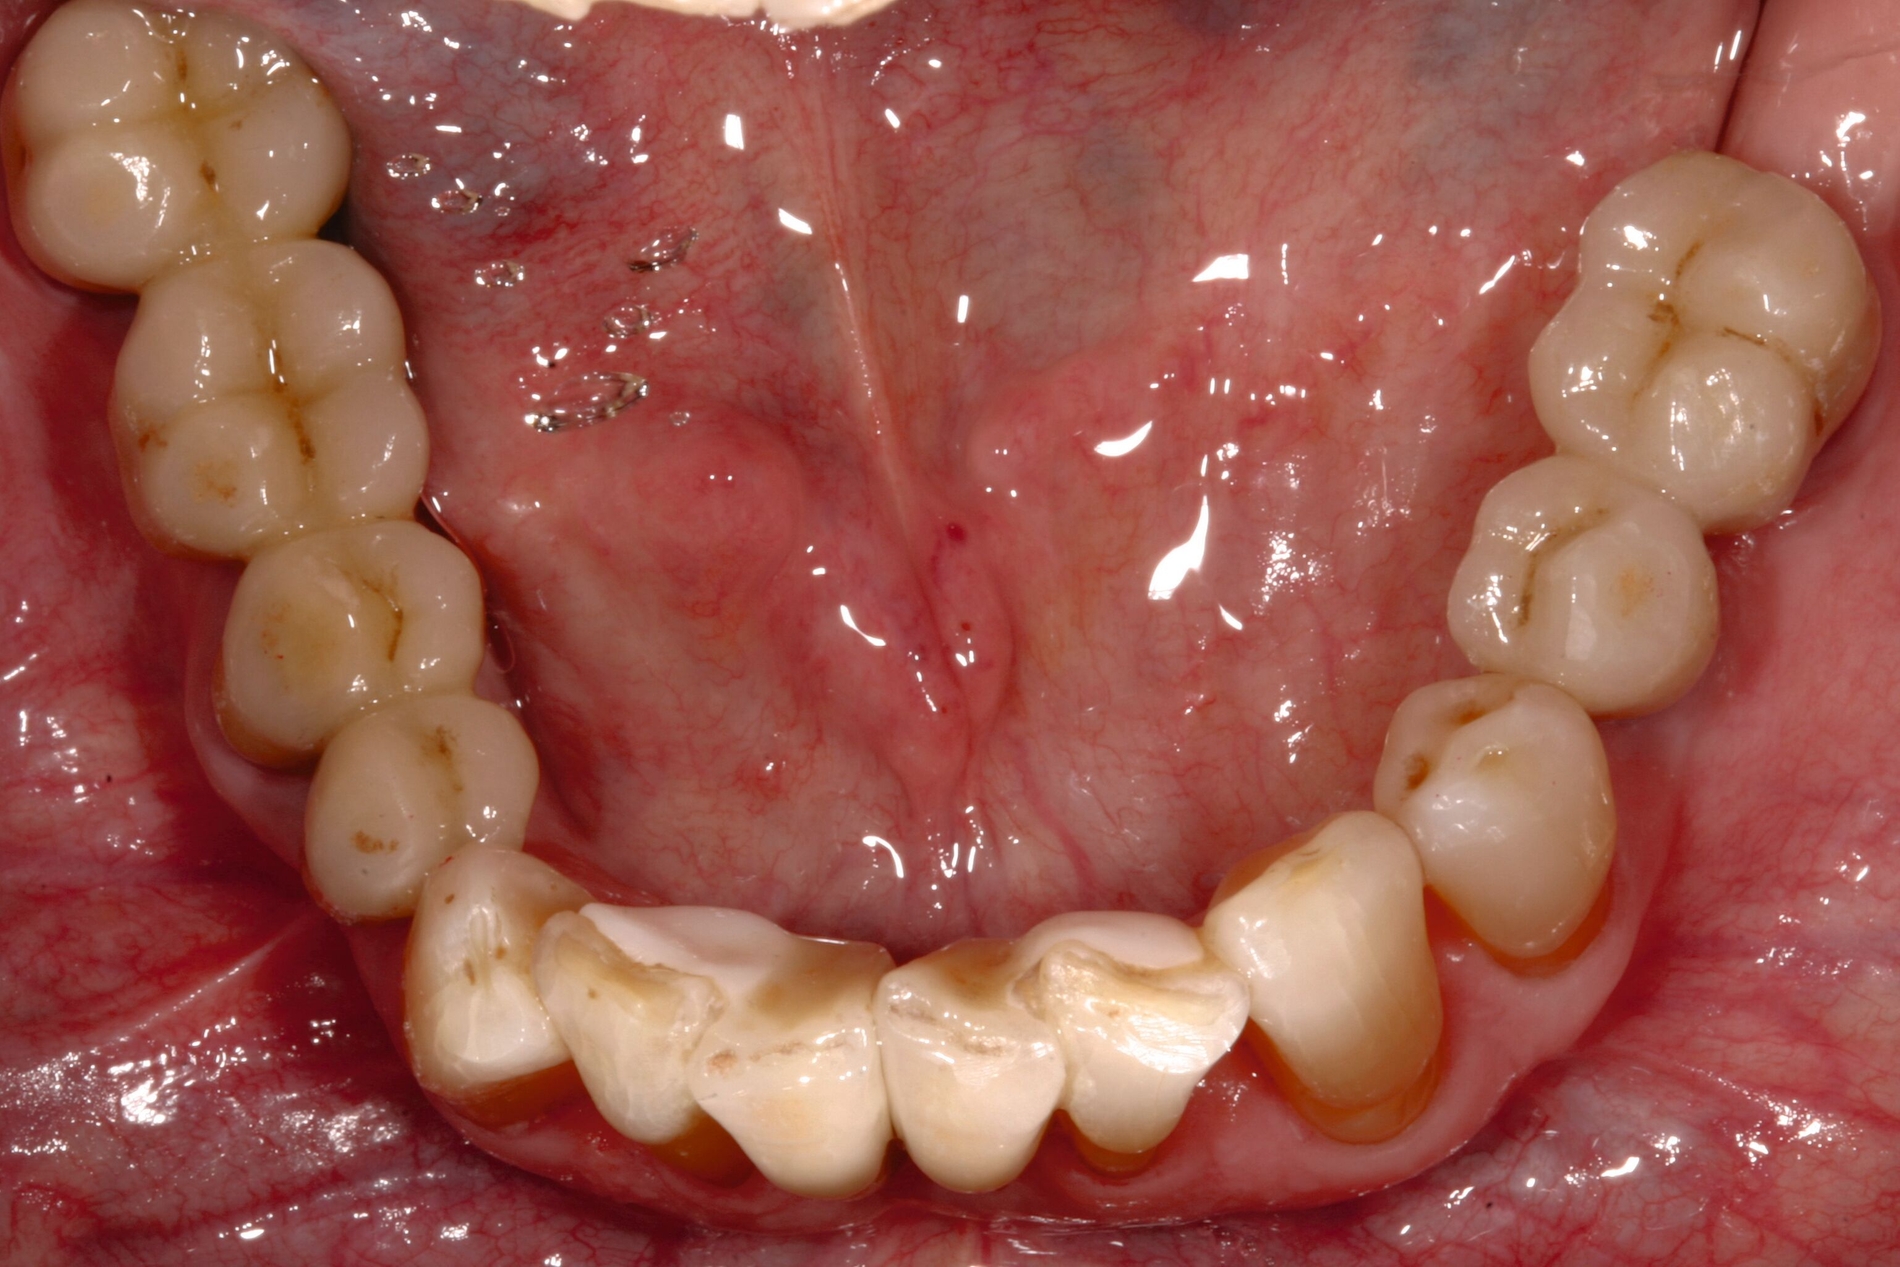

Der Patient wies verkürzte Zahnreihen im Ober- und im Unterkiefer sowie zusätzliche Schaltlücken im Unterkiefer auf (Abbildung 9). Nach Abschluss der ersten beiden Stufen der Therapie (nicht-chirurgische Parodontitistherapie), die darauf abzielte, alle vorhandenen Zähne zu erhalten, wurden an allen Zähnen Sondierungstiefen von maximal vier Millimetern erreicht. Anschließend erfolgte die Planung des definitiven Zahnersatzes im Sinne der aktuellen Leitlinien-Empfehlungen:

Ein Ersatz der Molaren war nicht erforderlich, da der Patient mit der verkürzten Zahnreihe seine Kaufunktion als ausreichend empfand. Aufgrund der erhöhten Beweglichkeit der Oberkieferfrontzähne, die die mundgesundheitsbezogene Lebensqualität stark beeinträchtigte, wurde eine adhäsive Schienung von Zahn 13 bis 21 durchgeführt. Dabei kam ein Polyethylen-Fasernetz (Ribbond, Seattle, USA) zum Einsatz (Abbildung 10). Zur Versorgung der Freiendsituation wurden zwei Implantate mit lokalem Knochenaufbau inseriert und mit implantatverankerten zementierten Einzelkronen versorgt. Die Frontzahnschaltlücke im Unterkiefer wurde mit zwei einflügeligen Adhäsivbrücken aus labial verblendeter 3Y-TZP-Zirkonoxidkeramik (Abbildungen 11 bis 13) geschlossen, die Schaltlücken regio 44 und 46 durch eine Anhängerbrücke, die von Zahn 47 bis Zahn 44 reichte (Abbildung 14).

Der Patient konnte über einen Zeitraum von mehr als 20 Jahren nachbeobachtet werden. In den ersten 14 Jahren stellte er sich jährlich in der Klinik zur unterstützenden Parodontitistherapie und Kontrolle der Restaurationen vor (Abbildung 15). Der parodontale Zustand konnte stabil gehalten werden und auch die prothetischen Versorgungen erwiesen sich komplikationsfrei.

Danach wurde der Klinikbesuch für den inzwischen 83-Jährigen zu beschwerlich, und er wurde von einem wohnortnahen Zahnarzt betreut. Die von ihm 19 Jahre nach Eingliederung des Zahnersatzes angefertigte Panoramaschichtaufnahme dokumentiert die unveränderte prothetische Versorgung des Unterkiefers sowie die stabile Situation der verkürzten Zahnreihe im Oberkiefer (Abbildung 16). Für eine detaillierte Darstellung des Fallberichts wird auf die Originalpublikation verwiesen [Wolfart und Kern, 2024].